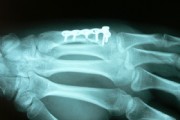

Fracture of the fifth metacarpal bone.

This young man fell off the skateboard and broke his fifth metacarpal. The conducted cast immobilization in the emergency hospital was found to be ineffective, because the bone was flexed too much.

After the straightening and plating the injury healed very well.